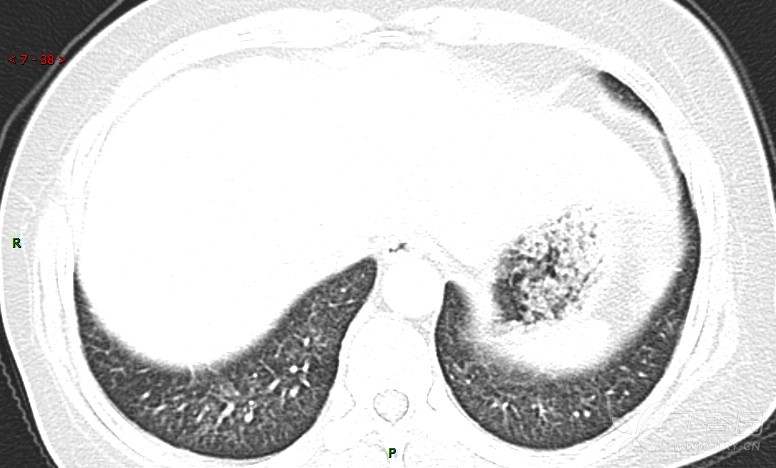

女性,58岁,阵发性咳嗽2月,加重1月。

患者于2月前无明显诱因出现咳嗽,以阵发性干咳为主,接触冷空气后咳嗽明显,偶咳少量白色泡沫样痰,咳嗽剧烈时感憋喘,无发热、盗汗,无头痛、头晕,无胸痛、咯血,无恶心、呕吐,无腹痛、腹泻,无尿频、尿痛等不适,于当地医院给予肌注及静脉药物治疗,具体药物名称不详,效果欠佳,近1月来患者咳嗽频率较前增加,咳嗽剧烈时感双侧季肋区疼痛不适,10余天前出现发热,体温在38℃左右,伴畏寒、寒战,无头痛、头晕,无纳差、乏力等不适,药物治疗后体温降至正常,仍阵发性咳嗽,今为求进一步诊治,就诊于我院急诊,因呼吸内科暂无床位,急诊门诊以“肺间质病变”收入急诊留观室,给予“抗感染、止咳”等对症支持治疗后,今日以“肺间质性病变”收入我科,患者自本次发病以来,神志清,精神可,饮食尚可,睡眠一般,大小便正常,体重较前无明显变化。

患者活检肺组织后行PET/CT检查